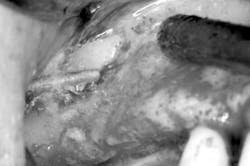

1. A full-thickness flap is reflected to gain access to the lateral wall of the maxillary sinus (Fig. 1). In this area the bone is normally very thin, usually less than 1 mm.Fig. 34. The sinus membrane is separated from the bony wall. Perforations of the membrane occur frequently during this phase. To increase safety and reduce complications, the air-driven sonic handpiece is used, coupled with the discoid insert. The insert is activated (vibrating and irrigated by the water spray) and then placed between the lateral bone wall and the Schneiderian membrane (Fig. 4).